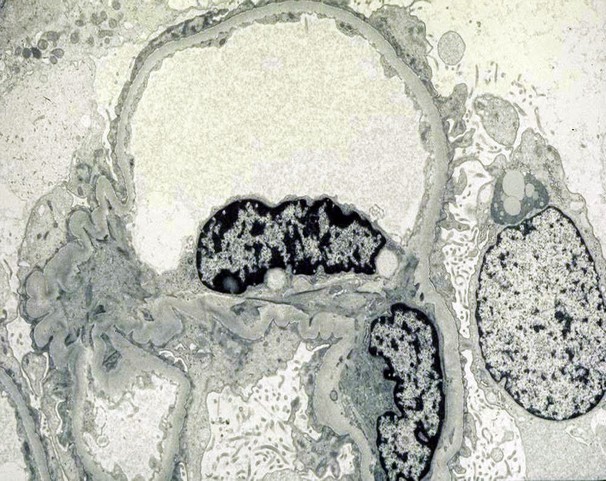

Electron microscopy: below

What is the diagnosis and treatment?

Minimal Change disease:

“Nil” disease= Proteinuria with epithelial cell foot processes fusion

Most common cause of nephrotic syndrome in children